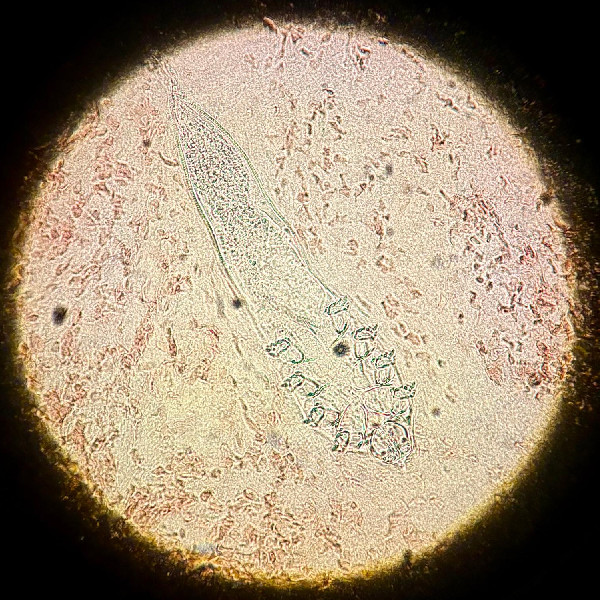

Inhoud comedo uitdrukken of haren uittrekken en onderzoeken op Demodex (in druppel NaCl onder dekglaasje). Of een stuk plakband gebruiken, omgekeerd bevestigen op objectglas en bekijken onder de microscoop. Of een biopt. De interpretatie is moeilijk omdat Demodex mijten normaal voorkomen op de huid van het gelaat. Als het er heel veel zijn, en het histologisch en klinisch beeld past niet goed bij een rosacea of bacteriële folliculitis, dan wordt de diagnose aannemelijk.

Demodex mijtDemodex mijt onder de microscoop